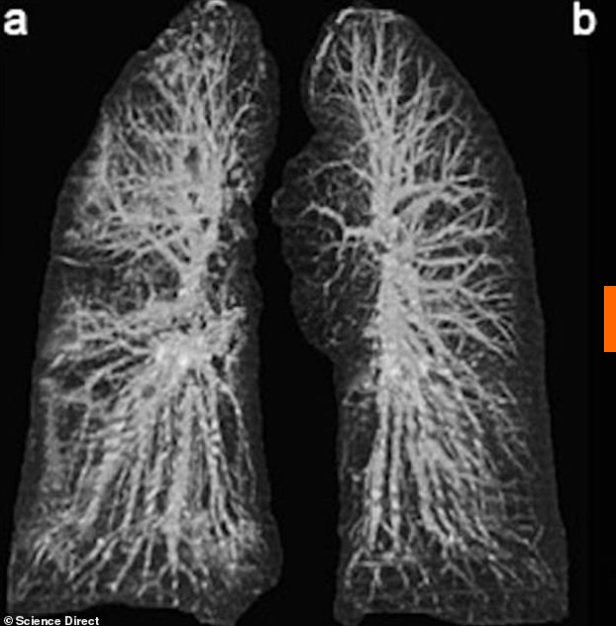

Οι ακτινογραφίες είναι από τον πνεύμονα ενός 60χρονου Κινέζου που βρέθηκε στην Ιταλία.

Στην πρώτη φωτογραφία φαίνεται ο πνεύμονας του την πρώτη μέρα που νόσησε ενώ στη δεύτερη φαίνεται όταν πλέον η κατάσταση έχει προχωρήσει.